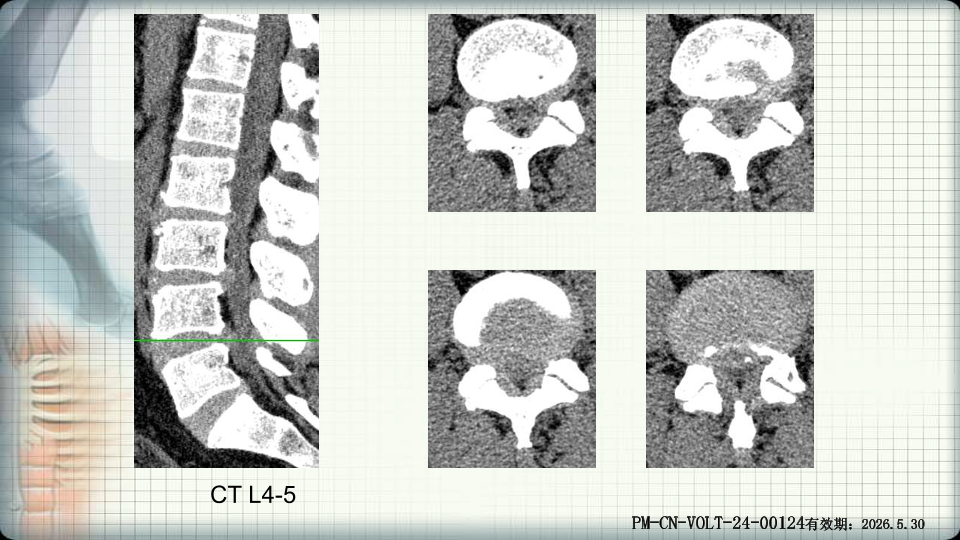

管狭窄症非手术治疗-谢学虎